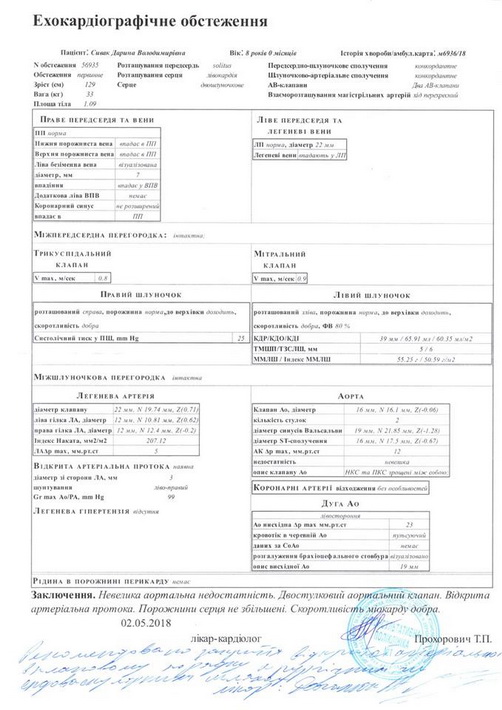

Останнім часом дитина почала швидко втомлюватись, скаржитись на погане самопочуття. Нещодавно при обстеженні було виявлено, що вона має дві вроджені вади серця, про які батьки раніше навіть не здогадувались: відкрита артеріальна протока та двостулковий аортальний клапан.

“Нещодавно ми були на консультації в двох київських кардіологічних центрах – в Науково-практичному медичному центрі дитячої кардіології та кардіохірургії та в Національному інституті серцево-судинної хірургії ім. М.М. Амосова. Кардіохірурги рекомендують якнайшвидше провести операцію із закриття артеріальної протоки. Вартість самого окклюдера складає близько 80 000 грн (без врахування інших витрат). Коштів на придбання окклюдера, а в подальшому – штучного аортального клапана для проведення операцій ми не маємо. Дуже сподіваємось на допомогу небайдужих людей. Будь ласка, врятуйте сердечко нашої донечки!”, – звертається до всіх небайдужих Анна.